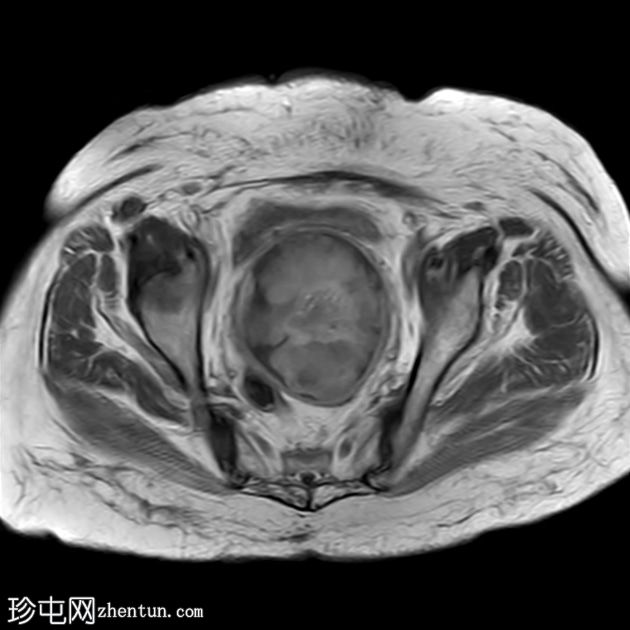

轴位

T2

子宫呈U形,宫底轮廓消失,宫底突出至扩张的阴道内,宫颈位于内翻的宫底上方(II级子宫内翻):

宫底处可见阴道内可见边界不清、分叶状实性肿块,明显扩张阴道壁,阴道壁完整。

肿块最大轴向及头尾径约为 9.7 x 9.6 x 9.5 cm,T1 加权像呈低信号,T2 加权像呈中/高信号,伴有扩散受限和不均匀增强。

肿块前方压迫膀胱,后方紧邻乙状结肠,未见侵犯。

肿块压迫左侧远端输尿管,导致轻度输尿管肾积水。

轴位MRI:可能显示靶环状或同心环状结构,提示子宫内膜存在不同层次。